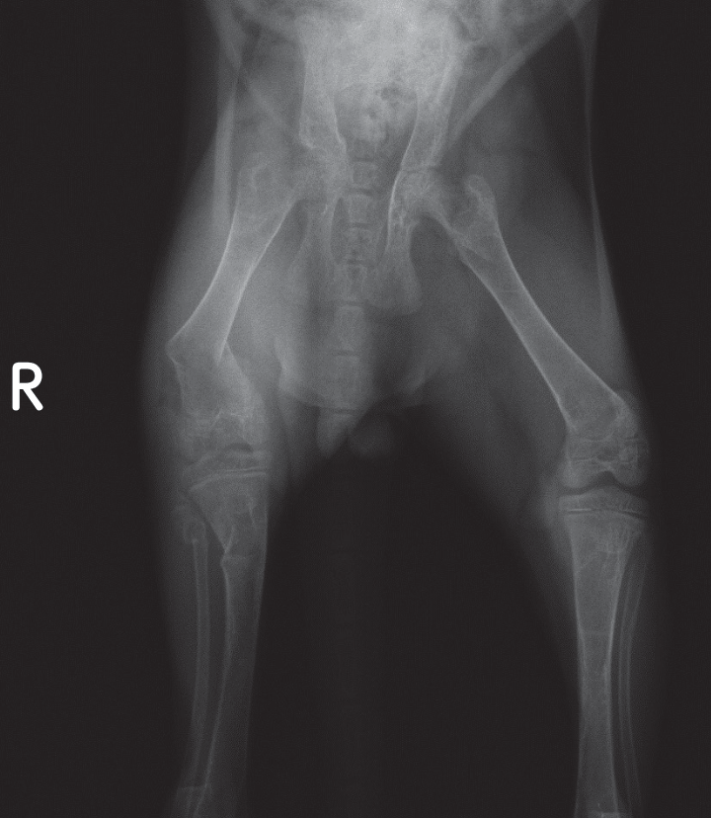

Kekurangan dan kelebihan kalsium juga berbahaya bagi anak kucing dan anjing. Kalsium berperan penting dalam pembentukan tulang, sehingga tulang yang kekurangan kalsium akan mudah patah dan sakit. Sebaliknya, pemberian kalsium berlebih juga membahayakan karena anak anjing belum bisa mengatur penyerapan kalsium dari usus. Pada anjing besar, pemberian suplemen kalsium sering menyebabkan gangguan pertumbuhan tulang.